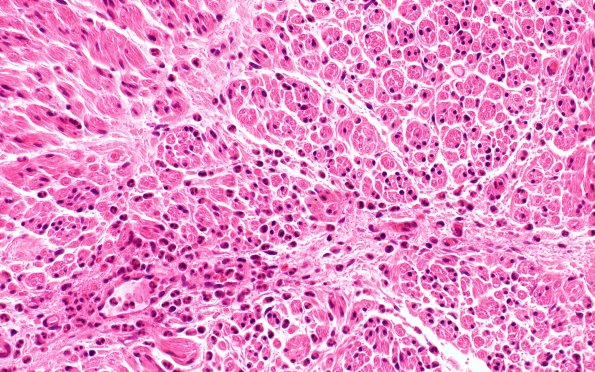

Washington University Experience | PERIPHERAL NEUROPATHY | 19 TRAUMATIC INJURIES | 20A2 Suprascapular nerve (Case 20) H&EBlkB 40X 2

H&E stained sections of the suprascapular nerve (neurosurgical specimen block B) show perivascular acute inflammatory cells in the endoneurium and perineurium, unaccompanied by other signs of tissue damage or necrosis. (H&E)